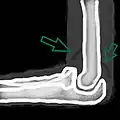

A traumatic right knee effusion. Note the swelling lateral to the kneecap as marked by the arrow.

A joint effusion is the presence of increased intra-articular fluid.[1] It may affect any joint. Commonly it involves the knee.